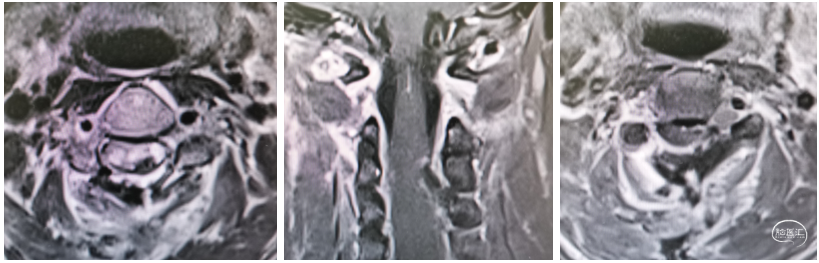

辅助检查:颈椎CT及MR示:脑干下份、C1-7水平脊髓上份见异常信号,累及长度约128mm,部分区域强化明显,内见病灶信号不均匀,增强见实性成分明显强化,相应水平脊髓肿胀等。

图1 颈椎CT及MRI示:脑干下份、C1-7及T1水平脊髓上份见异常信号,考虑室管膜瘤可能性大。